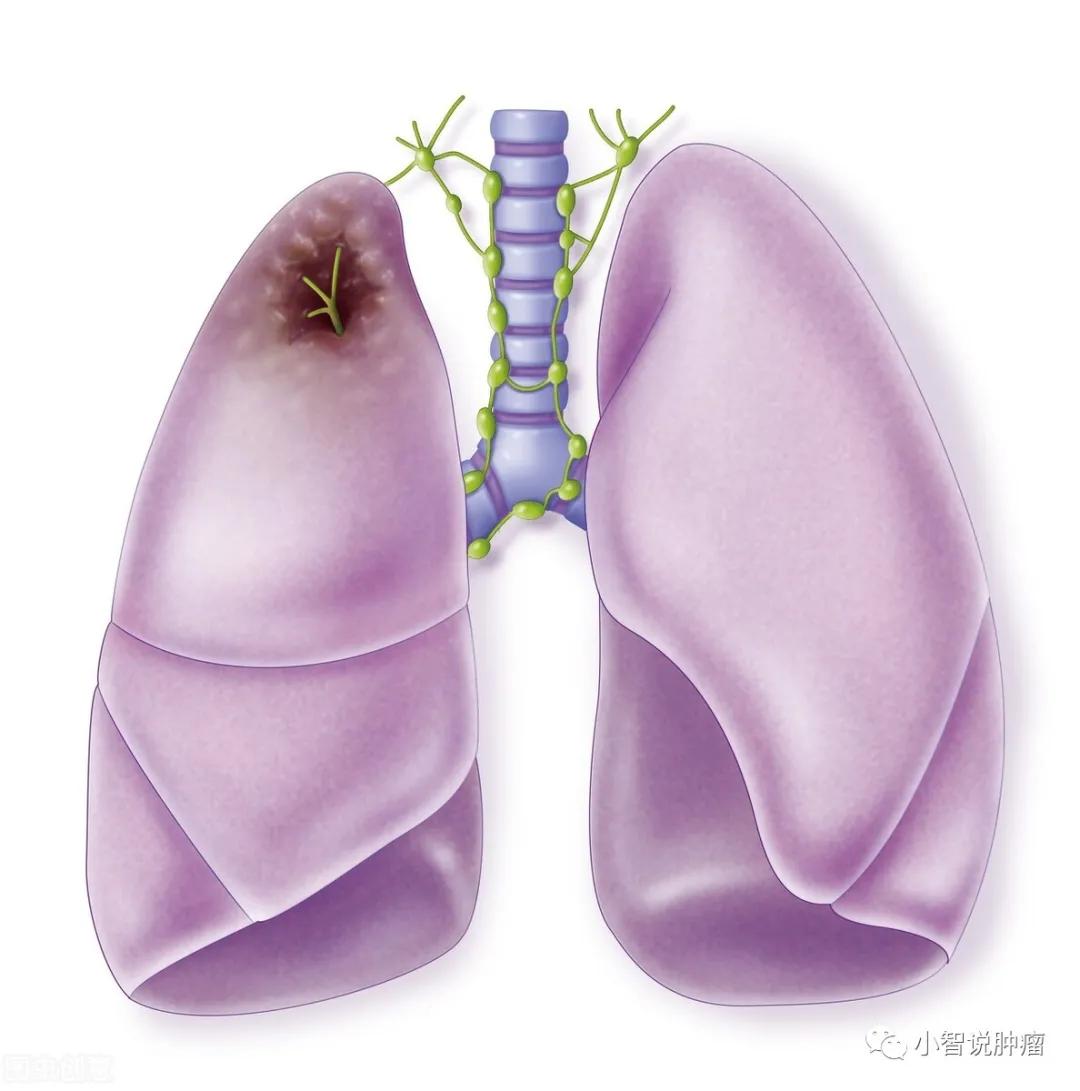

可见,肺一旦生了大病,尤其是肺癌,有空气也难以保证我们的生命安全!2020年我国癌症死亡人数约300万, 肺癌死亡人数以高达71万碾压其他癌种 ,遥遥领先。

早期肺癌超过90%的临床治愈率 ,多么可喜的数据!遗憾的是,早期肺癌大多没有典型症状,等到症状明显的时候,多进入了中晚期,治疗效果是大打折扣。

大家看这幅图片就能看出,普通胸部X线与低剂量螺旋CT最大的不同就是,它是 整体重叠的结构 ,而不是切片。由于前后组织结构的重叠干扰,这样就会导致隐藏在肺组织中间的微小病灶被遗漏,不利于肺癌的早期发现。